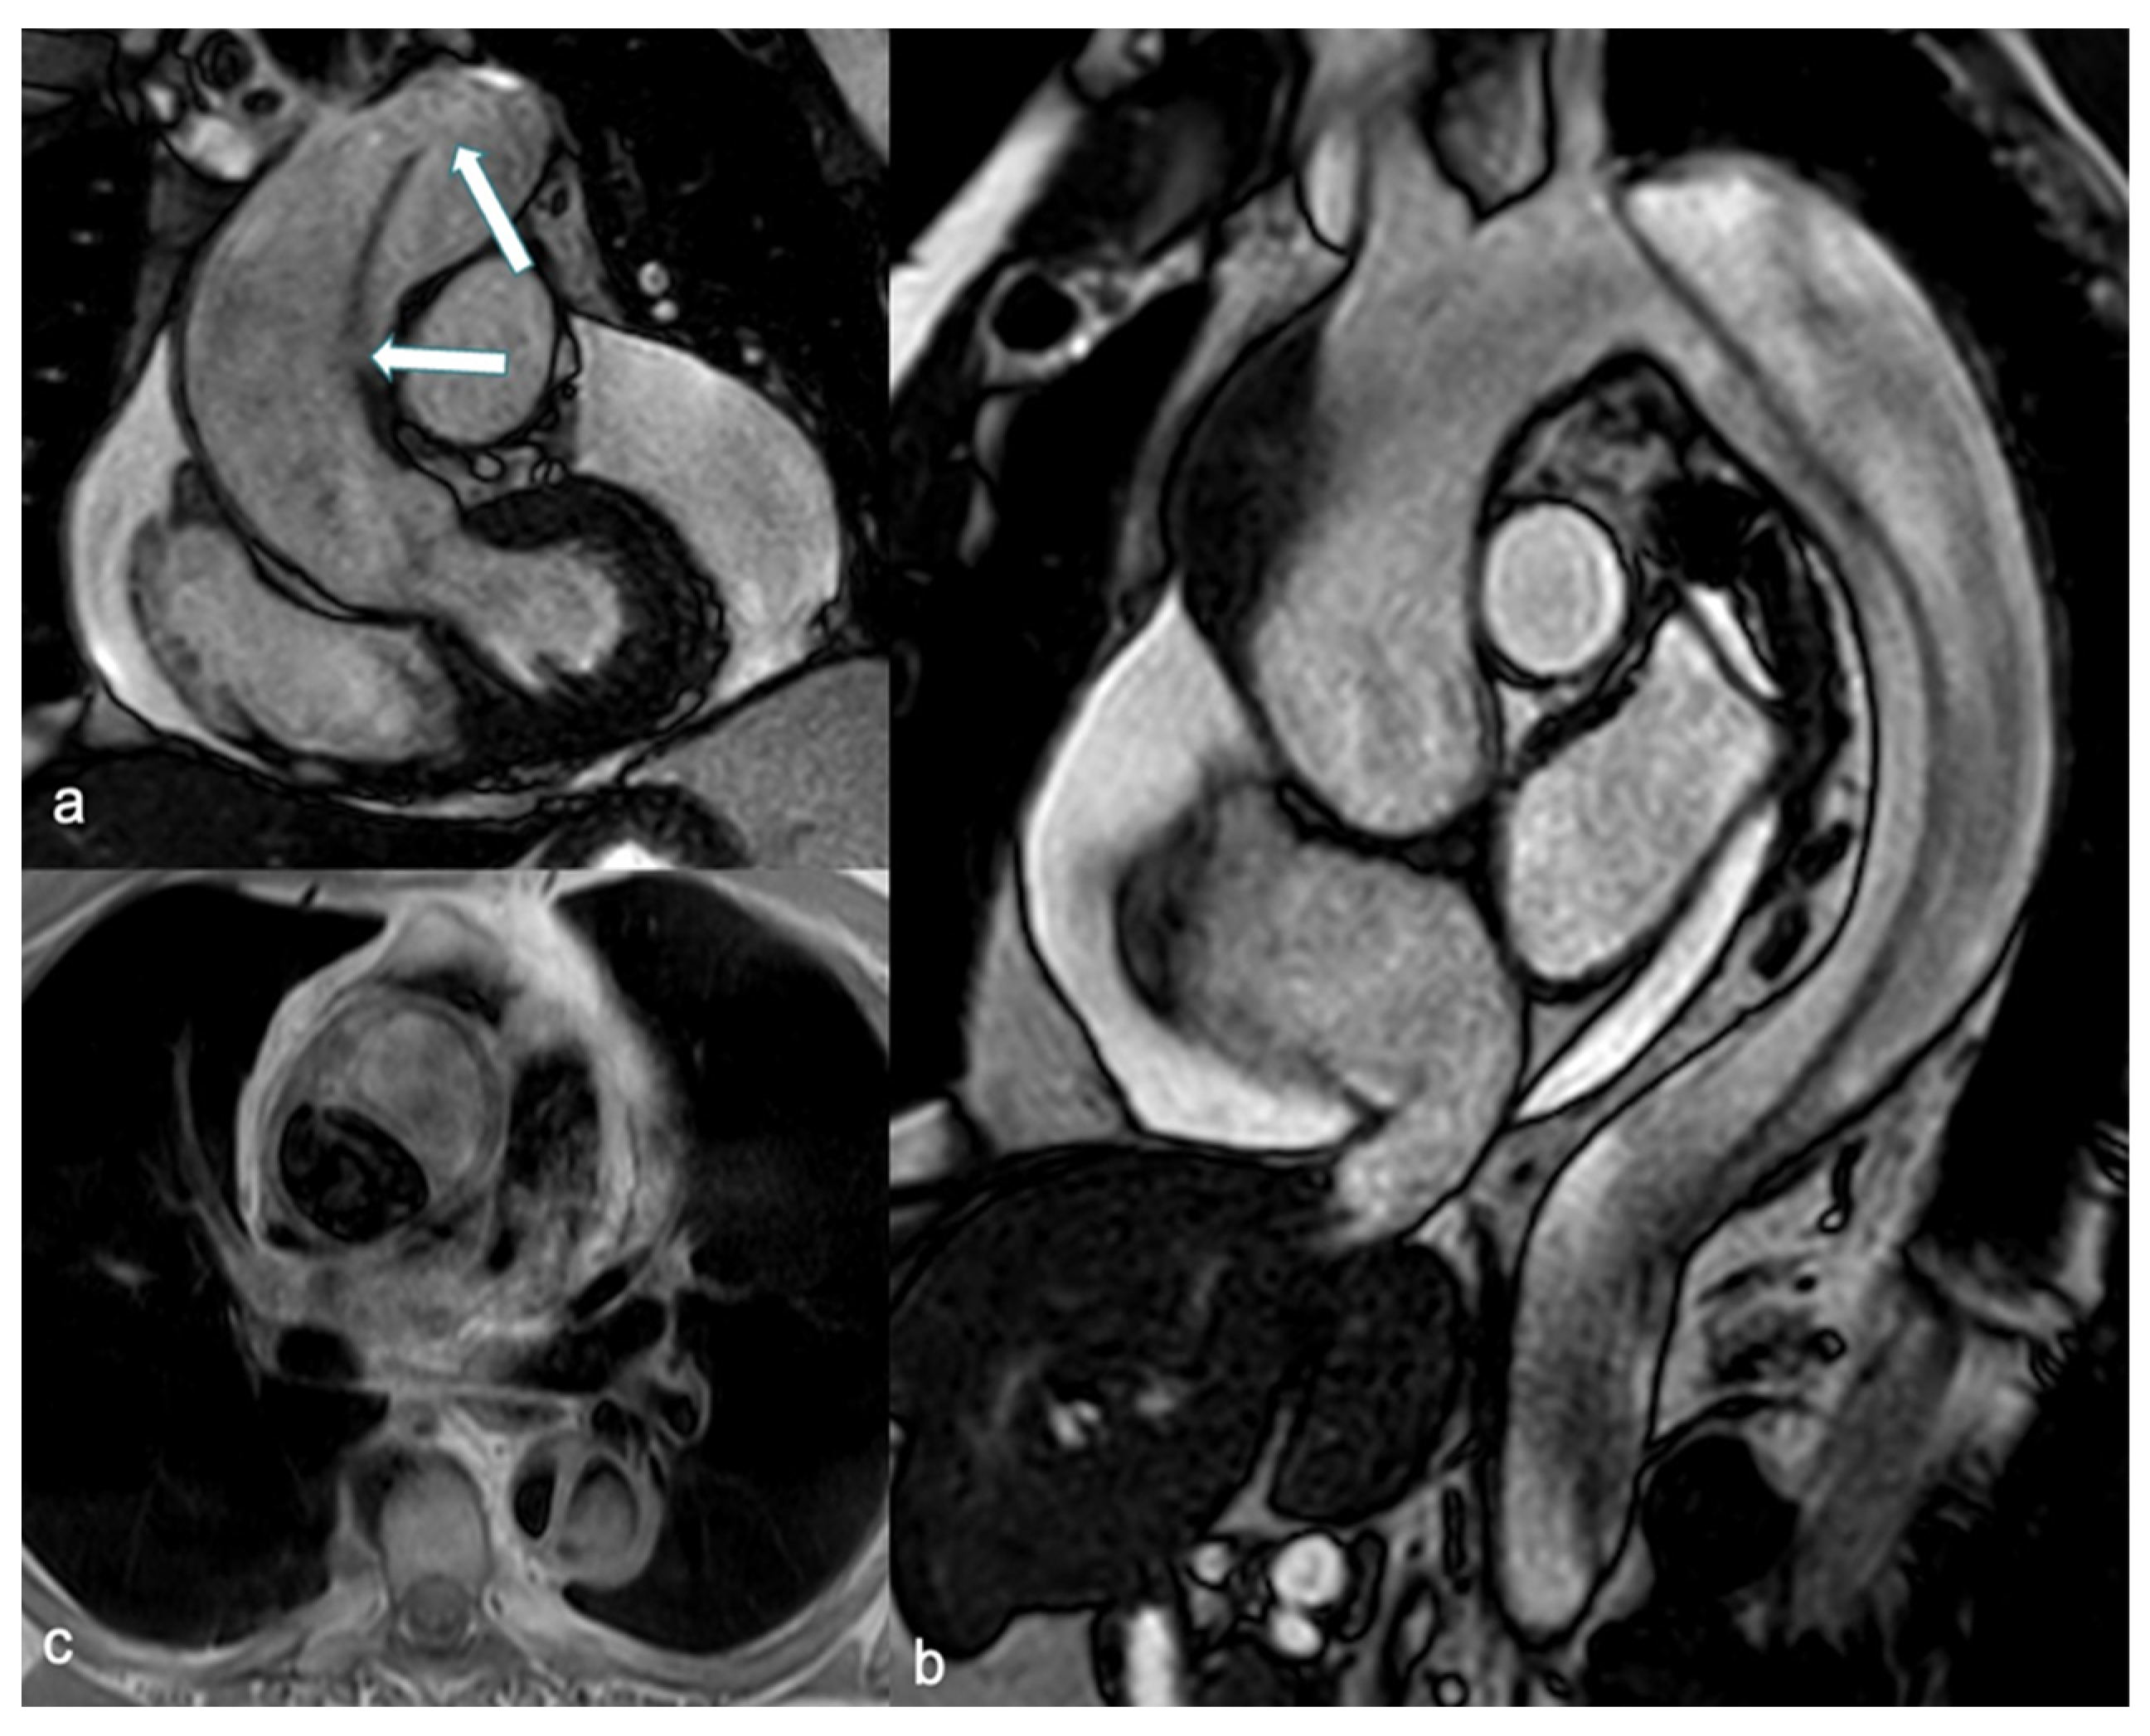

MRI provides comprehensive imaging of the entire aorta and its branching vessels, characterizing aortic wall changes and offering physiological evaluation of valve function, along with flow quantification. These attributes position MRI as a valuable alternative to CT. In the elective setting, the use of MRI without gadolinium is recommended in pregnant patients with aortic disease who require surveillance imaging of the aortic arch, descending aorta, abdominal aorta, or all three (Class I, Level of Evidence C) [5]. However, limitations include lower accessibility, longer examination times, reliance on patient cooperation, and challenges in monitoring and treating unstable patients during the procedure. Consequently, MRI is not commonly utilized in emergency departments (ED) for diagnosing AAS [73]. Nonetheless, it could be particularly beneficial for pregnant women with suspected AD, especially considering the availability of techniques for aortic depiction that do not require the administration of CAs. Spin echo-black blood acquisitions enable clear delineation of aortic shape and diameter, as well as the identification of wall structure alterations. The false lumen can be identified by increased intraluminal signal intensity, attributable to slow flow, and can be characterized by web-like remnants of dissected media (Figure 4) [74].

Figure 4.

SSFP breath-hold images in coronal (a) and sagittal (b) views demonstrate an intimal-medial flap involving the entire thoracic aorta, including the ascending aorta, consistent with a Stanford Type A dissection. Multiple intimal tears are visible within the flap (arrow in (a)), and massive circumferential pericardial fluid is associated. An axial SE-BB image (c) shows a hypointense true lumen and increased signal intensity in the false lumen due to slow flow. SSFP: steady-state free precession and SE-BB: spin echo-black blood.

Unenhanced SSFP sequences provide accurate and reproducible aortic measurements as well as clear visualization of the intimal-medial flap (Figure 4) [75]. Additionally, cine SSFP MRI can delineate the entry and exit zones of the intimal-medial flap and detect aortic regurgitation by identifying flow turbulence. Pereles et al. demonstrated that a short imaging protocol combining single-shot true fast imaging with steady-state precession (FISP) and cine true FISP sequences is promising for the initial, rapid, and accurate diagnosis of aortic dissection and aneurysm in less than four minutes [76]. Finally, phase contrast sequences can provide quantitative data on flow velocity and volume in both the true and false lumen.